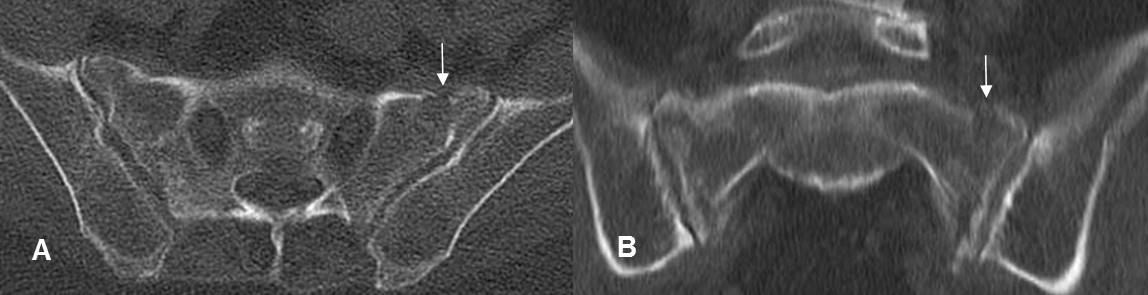

A: TAC axial y B: TAC reconstrucción coronal. Fractura en la parte superior del sacro.